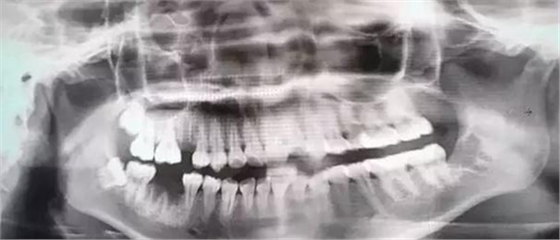

由于智齒的生長位置特殊,導致了拔除難易不同,如智齒出現(xiàn)橫著長或者靠近牙神經(jīng)的話,則難度會較高,一般人只需拍個口腔全景片,但相對于智齒靠近神經(jīng)管的情況,還可能需要拍CT,這都很考驗牙醫(yī)的技術(shù)。

下面這兩張圖,據(jù)說拔牙費時1.5小時,收費14000元。